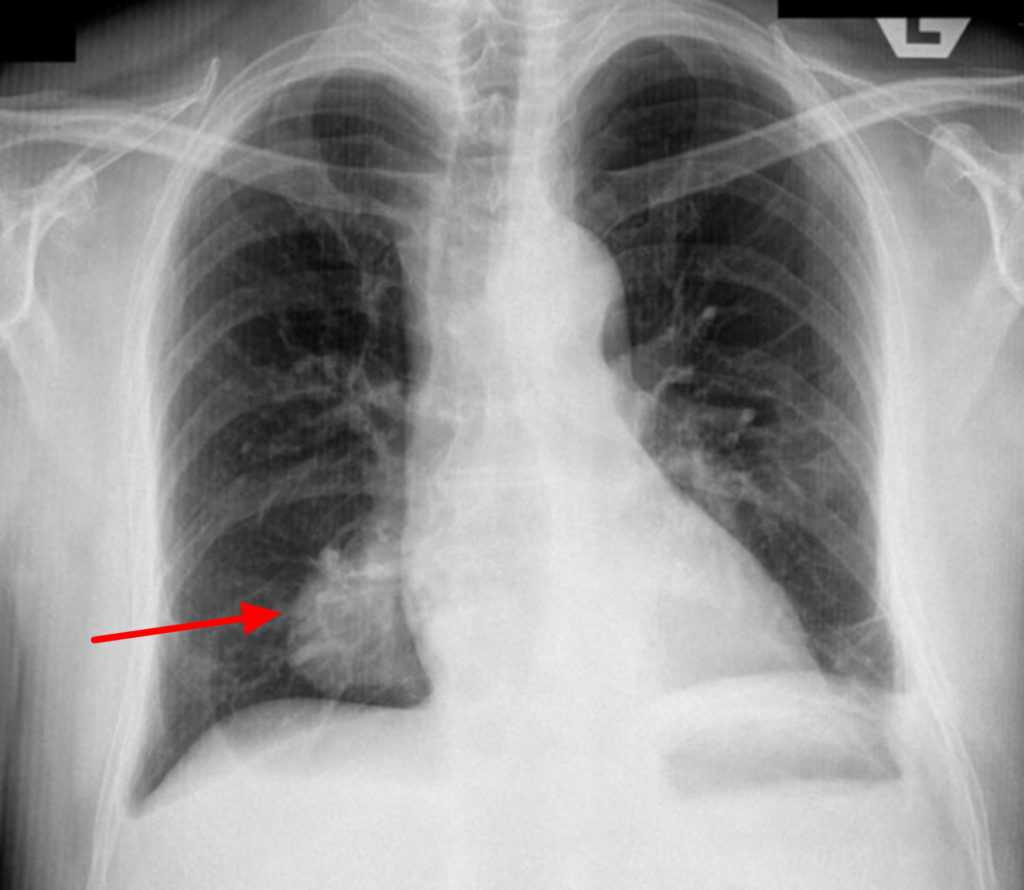

Что такое дисковидный ателектаз на рентгене

Дисковидный ателектаз относится к специфической картине коллапса легкого, которая проявляется в виде дискообразного или пластинчатого затемнения на рентгеновском снимке. Этот тип ателектаза часто наблюдается в нижних отделах легких и обычно связан с хроническими заболеваниями или длительной неподвижностью.

Дисковидный ателектаз на рентгене